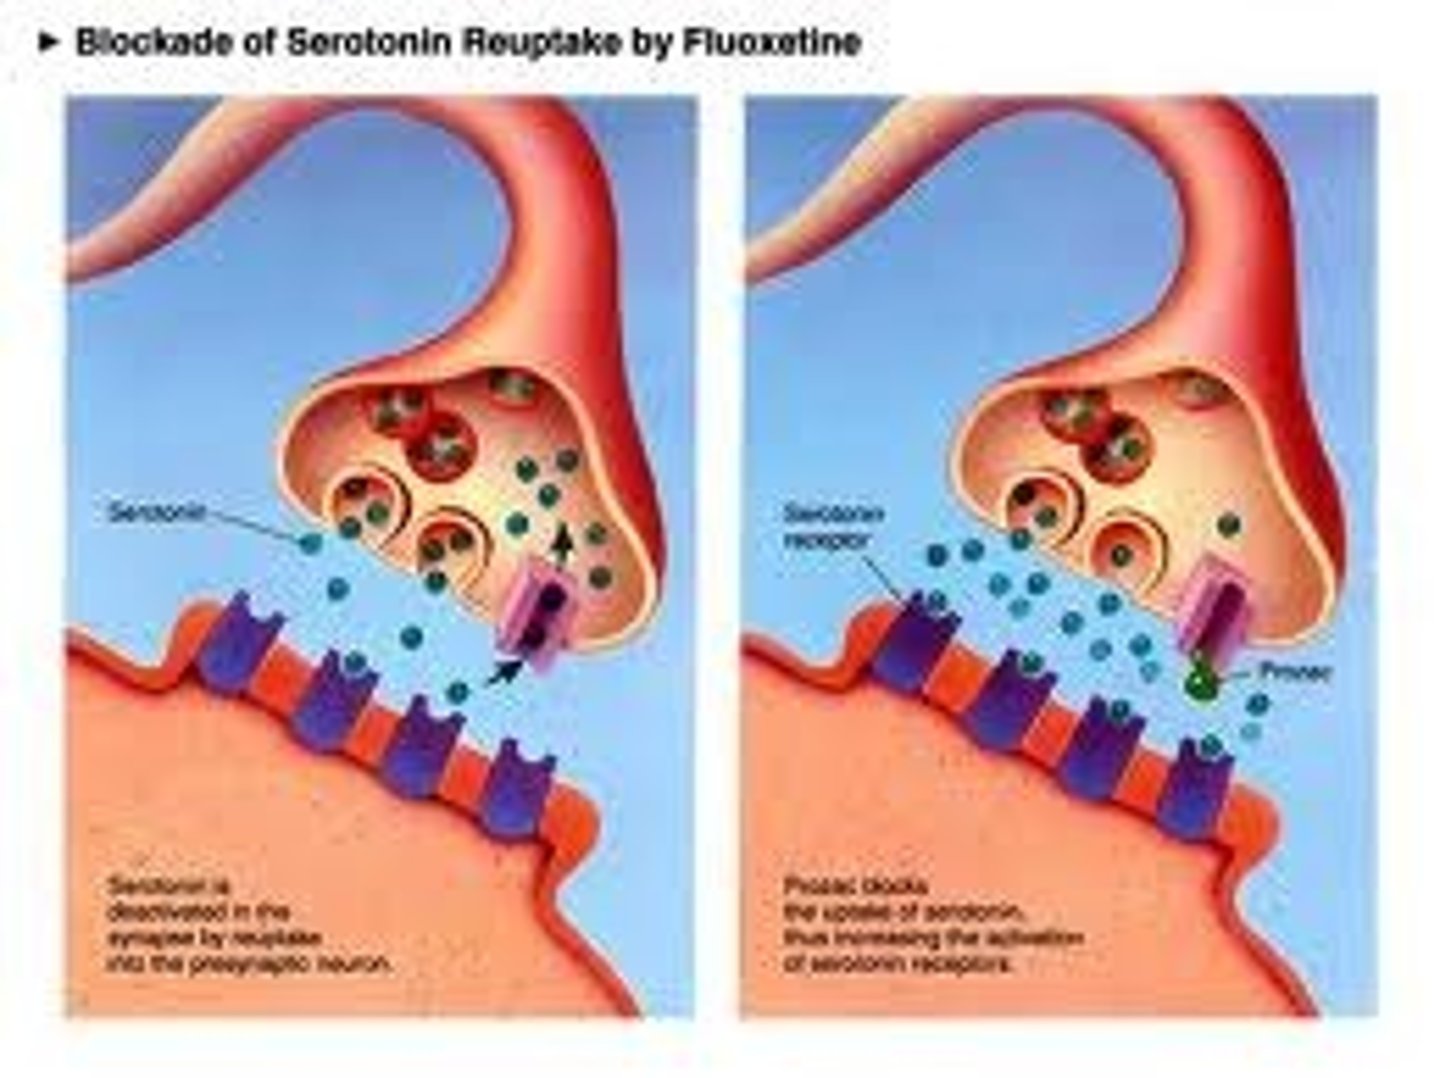

Reuptake

reabsorption of a neurotransmitter by the sending neuron after it completes its work

Reuptake inhibitors

drugs that interfere with the reabsorption of neurotransmitters in the synapse so that a greater amount remains in the synapse